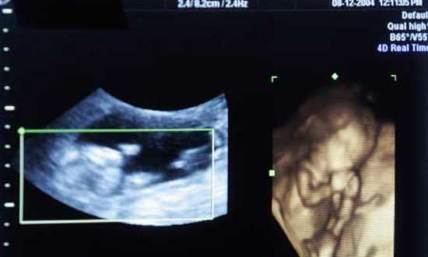

Texas began enforcing a new law mandating abortion providers show or verbally detail to women seeking the procedure an ultrasound image of the unborn baby.